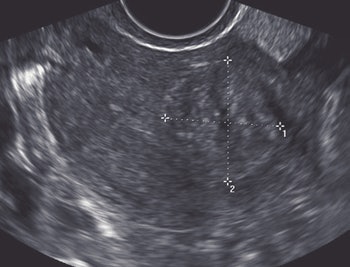

![]() |

| A 31-year-old woman who presented with infertility. Above, transverse view through uterus shows no abnormality. Below, reconstructed coronal view of uterine cavity shows arcuate uterus. Benacerraf B, Shipp T, Bromely B, "Which Patients Benefit from a 3D Reconstructed Coronal View of the Uterus Added to Standard Routine 2D Pelvic Sonography?" (AJR 2008; 190:626-629). |